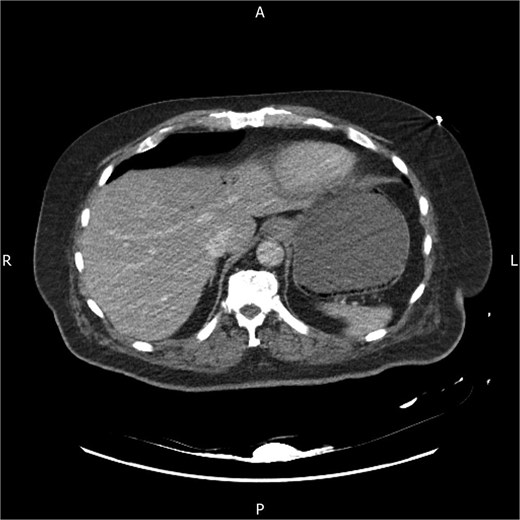

Following discussion with the referring team, the CT images were re-reviewed by a gastrointestinal radiologist. An addendum reported portal venous gas, gas within the left and right gastroepiploic vessels and submucosal gas within the stomach, consistent with acute gastric distension and emphysematous gastritis in a diabetic patient (Fig. 1). Piperacillin–tazobactam replaced amoxicillin–clavulanate to broaden gram-negative and anaerobic cover, and intravenous proton-pump inhibitor therapy was continued. Chest radiography showed left lower-lobe consolidation and he was treated for aspiration pneumonia. The oesophago-gastric team, noting his stability, frailty, high anesthetic risk and lack of peritonism or perforation, advised conservative management with nasogastric decompression and antibiotics, and outpatient oesophagogastroduodenoscopy once recovered.

Axial contrast-enhanced CT abdomen on admission showing mottled intramural gas within the gastric wall and associated hepatic portal venous gas in the left lobe, in keeping with emphysematous gastritis.

This case highlights key features of emphysematous gastritis and its care in frail surgical patients. Emphysematous gastritis is rare, but more frequently recognized with modern CT [1, 2, 6, 7]. It results from mucosal injury with invasion by gas-forming organisms, often in the setting of diabetes or immunosuppression [1, 2, 6, 7]. Affected patients are usually systemically unwell, unlike those with benign gastric emphysema [3, 6], and imaging typically shows mottled intramural gas with wall thickening, sometimes with portal venous gas as in this case [3, 6, 7].